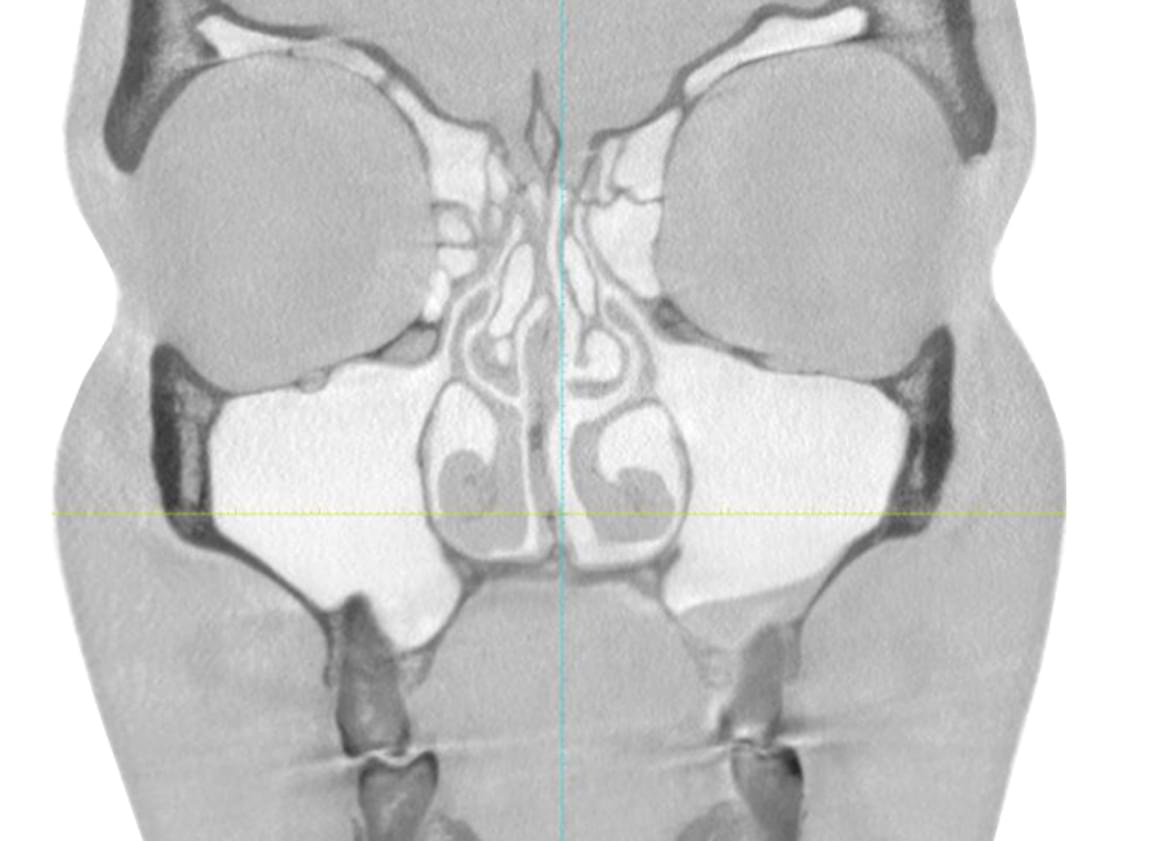

Výpočetní tomografie

(3d čelisťové snímky a snímky ústní dutiny)

CBCT Maxilofaciální diagnostika